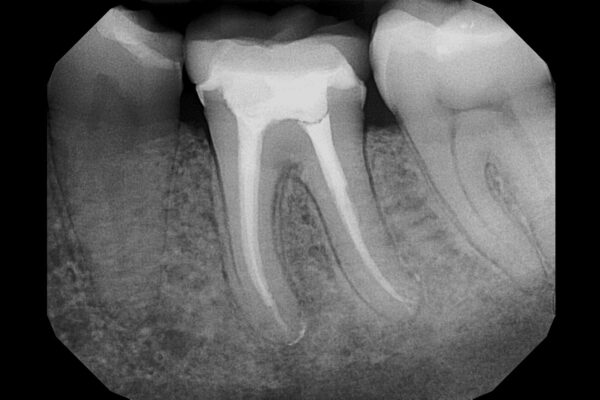

Rotary Instrumentation May Improve Pediatric Root Canal Outcomes, but Standardized Research Needed: Study